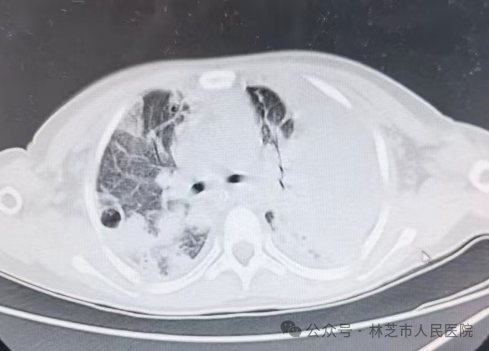

入院后胸部CT:重症肺炎